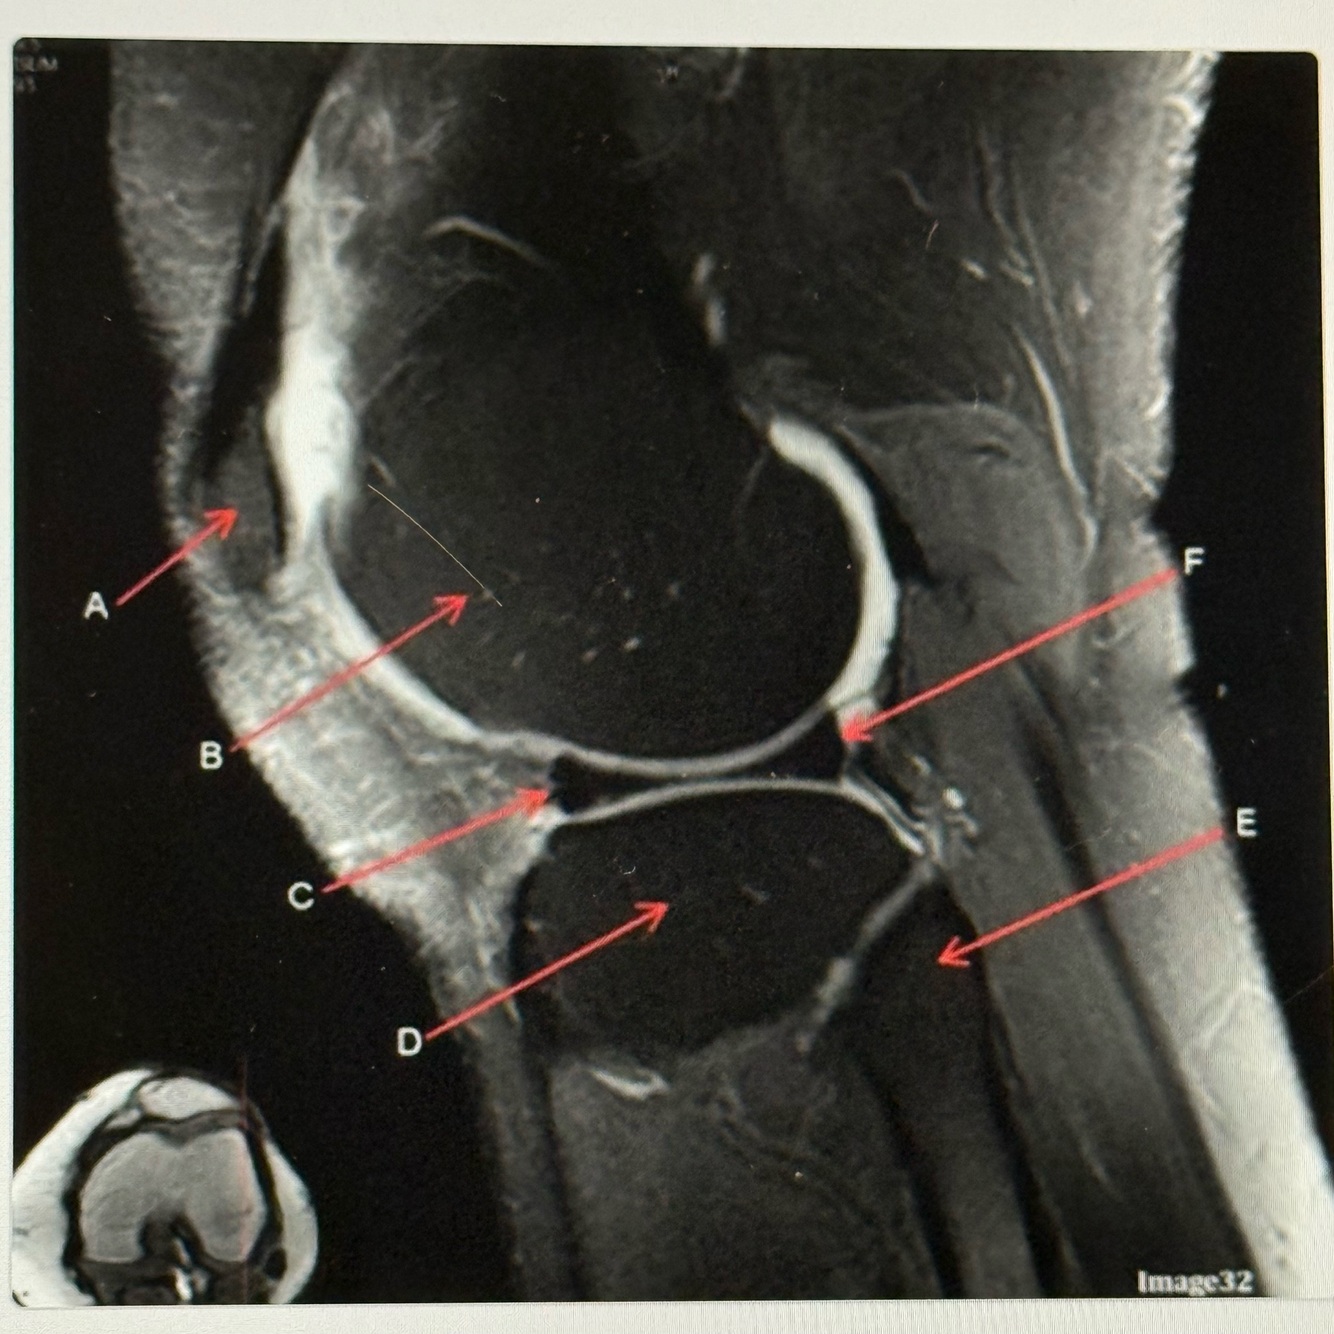

Q

Letter C points to the

A

Patellar tendon

17

Letter D points to the

Tibia

18

Letter E points to the

Posterior cruciate ligament (PCL)

19

Letter F points to the

Femur